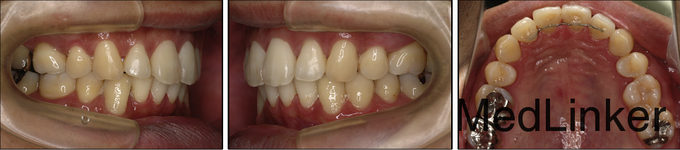

男,31岁,要求关闭牙弓内间隙

凸面型,骨性II类,青少年期拔除了3颗前磨牙但由于其他原因未继续矫正,深覆合,覆盖5.5mm,右侧磨牙I类,左侧磨牙II类关系,双侧尖牙II类

诊断:骨性II类,安氏II类,牙列间隙 治疗:上颌先上.022直丝拖槽,14niti排齐整平,依次换丝,为打开前牙咬合,16*22TMA弯制压低辅弓,如图。打开咬合后,粘接下颌拖槽,继续矫正。